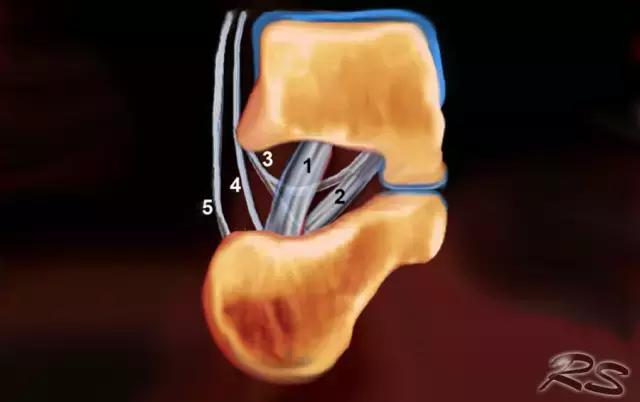

跗骨窦

跗骨窦是锥形空腔,在后内侧到前外侧方向上延伸。它位于距骨的颈部和跟骨的前上表面之间的脚的外侧面。跗骨窦内侧继续作为跗管,这是距骨与跟骨间一个漏斗形的空间。它包含脂肪,动脉吻合,关节囊,神经末梢和五个韧带结构 - 下伸肌视网膜的内侧,中间和侧根; 颈韧带; 和骨间骨骨膜韧带(图)。

这个空间可以是脚部疼痛在跗骨窦综合征的原因。治疗的第一步是用epomedrol和局部麻醉剂(利多卡因)的混合物封闭治疗。这针对外科医生在非引导方法中可能是挑战性的,但是用超声引导相当容易和准确地实现。

超声引导的跗骨窦的注射在右手侧与外侧入路。探头保持在冠状倾斜平面中。针沿着探头的长轴引入。

使用超声波可以容易地视察窦性骨壁。患者转向对侧,将待治疗的足以其内侧表面靠在桌面上,脚的外侧位于最上面。探头保持在关于脚的冠状平面中。

在跗骨窦被识别为跟骨的前处理和距骨颈之间的三角空间。针(箭头)的前端的锥形跗骨窦,这是由距骨(T)和跟骨(C)的边界内可以看到。

根据炎症的程度,可能存在空间的充血,并且可能存在中间血管可见,这是人们希望避免的。但是这又是比较容易的,特别是彩色多普勒。